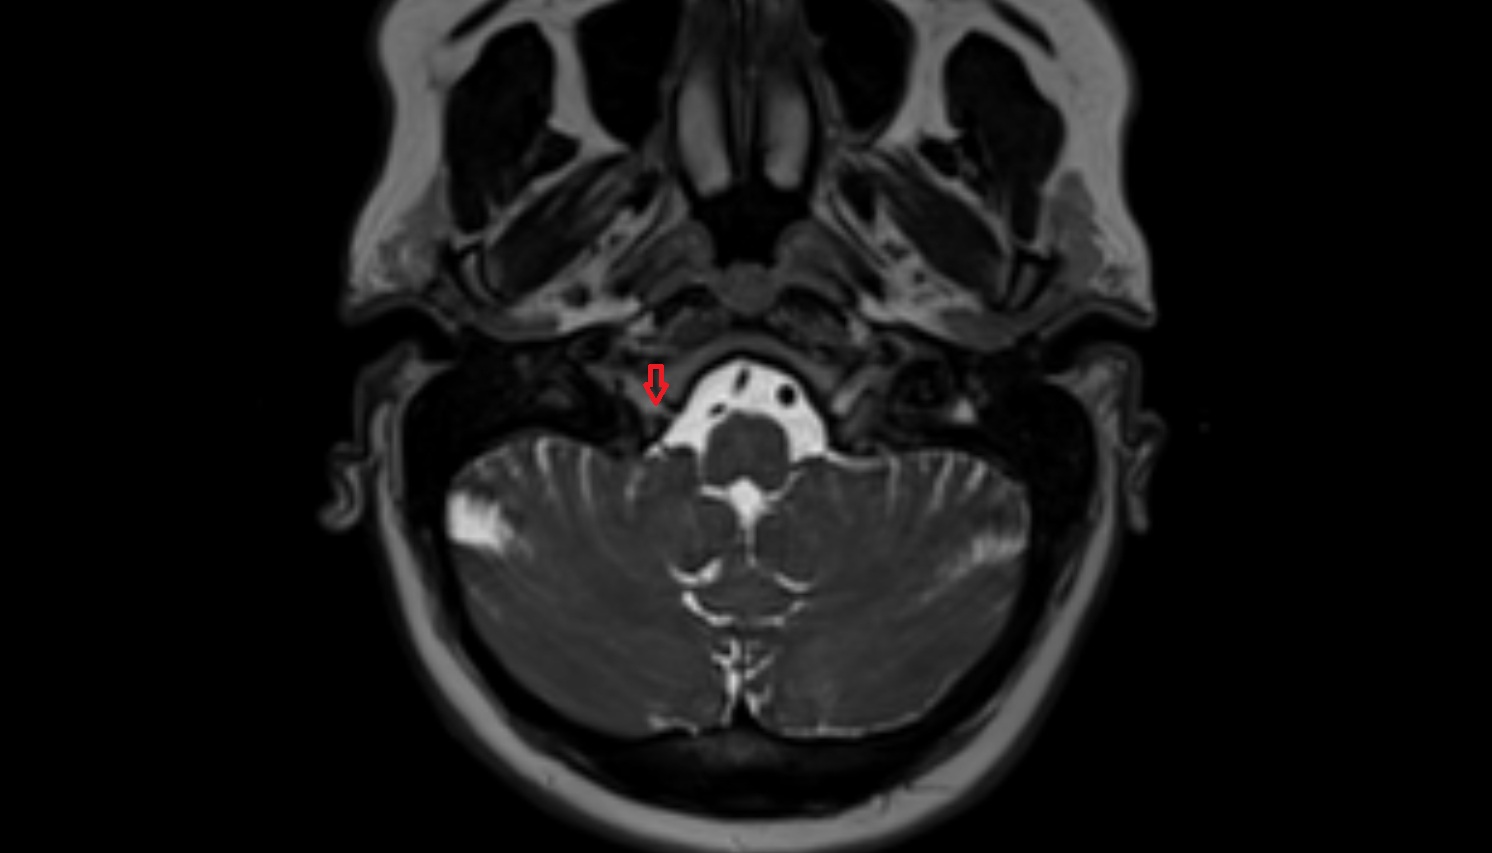

- Pons

- Premedullary cistern

- Cerebellopontine cistern

- Prepontine cistern

- Pontocerebellar cistern